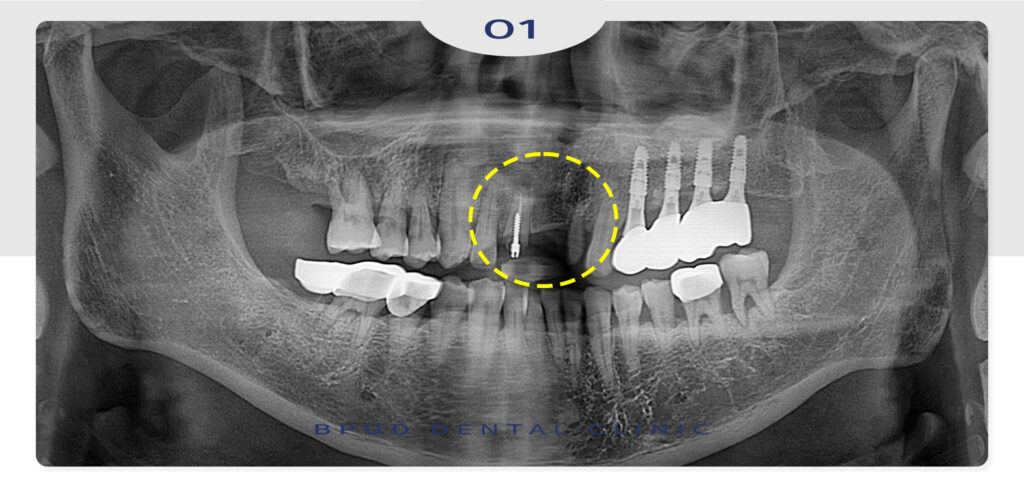

예후가 좋지 않은 앞니를 발치하고

바로 임플란트 식립을 진행한 모습입니다.

앞니 임플란트의 경우 발치 후 임플란트 완성까지

하루 안에 해결되는 원데이 방식으로 진행하는 것이

좋은데요.

하지만 이는 고난이도 술식에 해당하므로